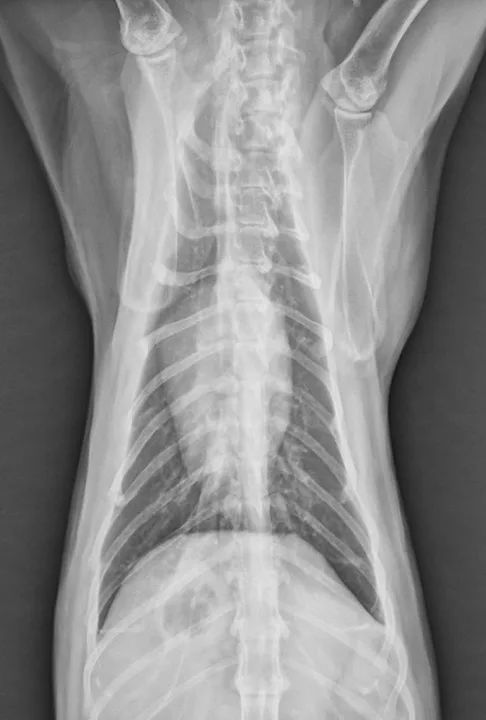

Featured Image

Figure 3

Dorsoventral radiograph revealing lytic lesions associated with distal phalanges consistent with digital metastasis. Image courtesy of Rachel Moon, DVM, DACVR

Feline lung-digit syndrome, a syndrome of multiple digital metastasis, is characterized by disseminated metastasis to the digits and is most commonly associated with bronchial and bronchioloalveolar carcinomas.1,3,5,6 This pattern of metastasis is most frequently diagnosed in older cats (mean age, 12 years; range, 2-20 years5), with no consistently reported breed or sex predilection.1,3-6 The pathogenesis is not well-understood; metastatic lesions are believed to arise via arterial embolization from the tumor.5,6 Tumor metastases are located at atypical sites, most notably the distal phalanges (Figure 3), with the weight-bearing third phalanx of the front feet most frequently affected.6 In addition, multidigit and multilimb involvement are common.6,7

Radiographs may reveal extensive osteolysis of the distal phalanx that may cross the joint space. Thoracic radiographs often show a single primary lung mass, although diffuse nodular disease has also been noted.1 No clinical signs of respiratory distress in affected cats have been reported.6